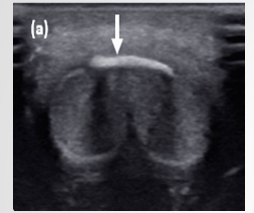

Patient attempting to urinate whilst penis erect. Heard ‘crack’ followed by acute pain

Normal anatomy at the base of the penis: Bilateral homogenous CC, Thin line of intact Tunica albuginea, Corpus spongiosm well demarcated

Mid shaft of penis defect noted with disruption of ventral tunica albuginea and left corpus cavernosum. Complex echogenic collection noted along left side of penile shaft

Defect in longitudinal measures 9.4mm. Hematoma noted ventral aspect.

Normal arterial flow noted in left cavernosal artery. Important to rule out vascular injury